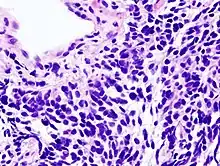

![]() | |

| Micrograph of a small-cell carcinoma of the lung showing cells with nuclear moulding, minimal amount of cytoplasm and stippled chromatin. FNA specimen. Field stain. | |